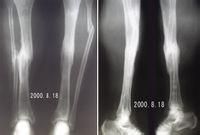

(一)彎曲型出生後脛骨下段向前彎曲,但無假關節,脛骨前弓處皮質增厚,髓腔閉塞,脛骨端萎縮硬化,呈前弓外形。發生骨折後,經一般處理局部不癒合,形成假關節。或因不認識此病,貿然作截骨手術,形成不癒合,繼續發展而兩斷端吸收,骨端硬化,遠端進一步萎縮變細,呈筆尖狀(圖1)。

先天性脛骨假關節圖1先天性脛骨假關節